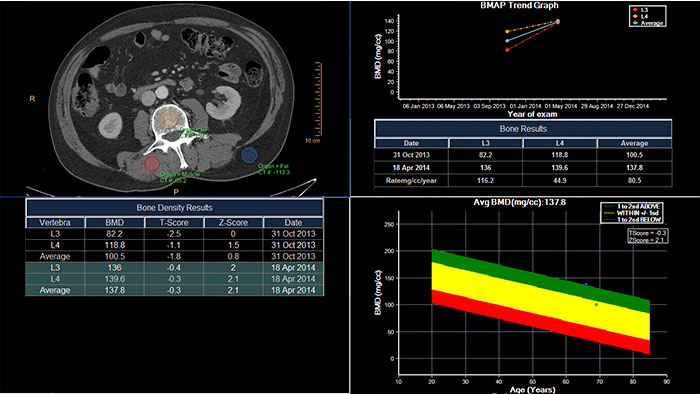

Track degenerative and metabolic bone disease

CT Bone Mineral Analysis (BMA) is designed to measure bone density in one or multiple time points. Using an internal reference method*, the application reduces reproducibility errors in multiple time point measurements and provides T- and Z- scores which help physicians assess the risk of osteoporosis.

*Muller DK, et al., Phantom-less QCT BMD system as screening tool for osteoporosis without additional radiation. Eur J Radiol. 2011; 79(3):375–81.